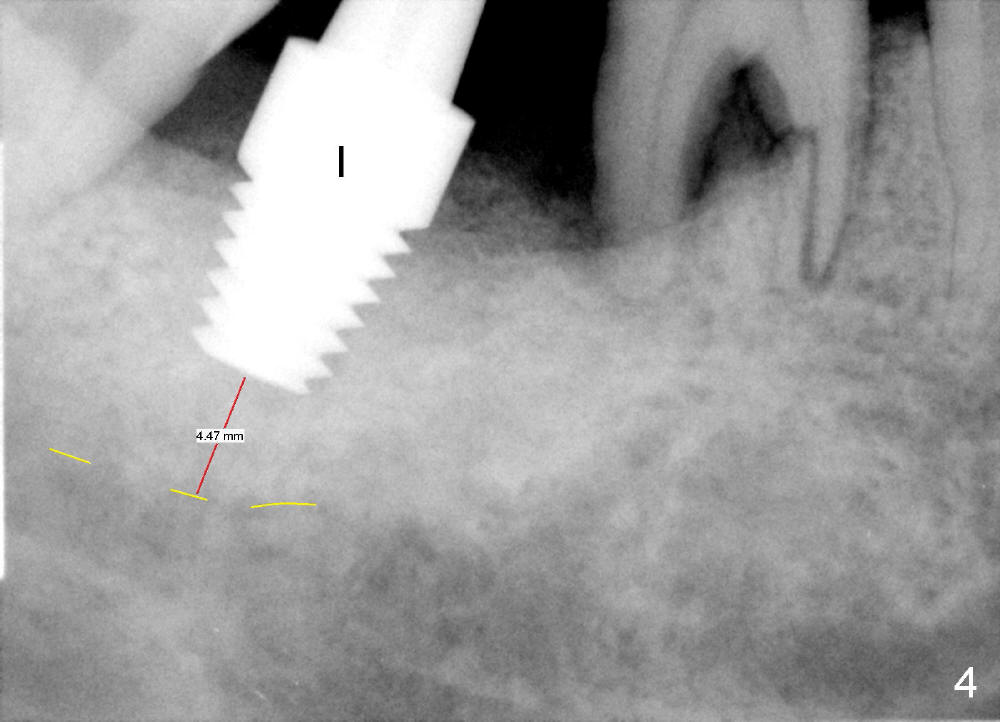

Luckily the patient returns for #31 implantation 4 months post socket preservation. Bone forms in the alveolus and above (Fig.1 black and white arrowheads, respectively). A 6 mm tissue punch is used to open the wound (Fig.2). Osteotomy forms using bone expanders, reamers and taps (Fig.3: 6x14 mm tap). Without infection, local anesthesia is more easily achieved than immediate implant when infection exists. The depth is controlled more readily with delayed implantation. Following adjustment of trajectory, a 7x11 mm implant is placed with insertion torque 60 Ncm (Fig.4 I). Fig.5 shows that the implant obliterates the wound; an abutment (A) is placed to retain perio dressing. With formation of new bone from socket preservation, insertion torque seems to be more easily obtained with the short implant. There is no space to re-use the harvested bone (Fig.6). The implant remains stable postop. Apparent new bone is forming toward the distal coronal threads 5 months postop (Fig.7). The bone around the implant remains stable 17 months post cementation (Fig.8), although there is an episode infection at the neighboring tooth (#30). The patient is more eager to have implants for the maxilla, since the flipper has lost. After implant placement at #7, the pain at #30 becomes more severe.